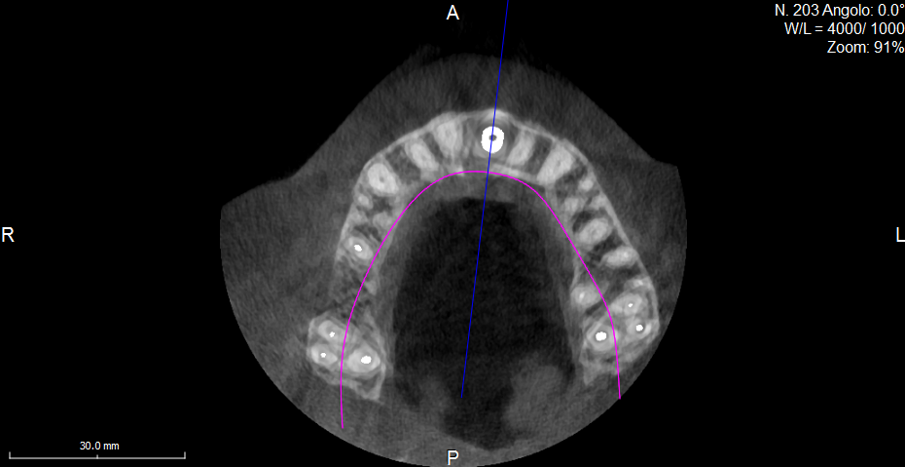

The intraoral scan is imported into CAD software and transformed into a virtual master model without the tooth to be extracted and a separate STL shape of the ideal CAD-designed tooth (Fig. 9). Now there is the opportunity for 3D evaluation of the dimensional relation between the new tooth and the soft tissue before extraction. In the current case, the tooth involved had not been extracted and a CBCT scan was performed (X-Mind trium, ACTEON; 110 x 80 mm field of view; 0.15 mm voxel size) for further investigation and treatment planning. In the AIS 3D App software that comes with the CBCT X-Mind trium device, STL files can be matched and aligned with the 3D bone volume, thus giving the opportunity to plan the future implant position taking into account the shape and position of the future crown (Figs. 10a & b). In accordance with the prosthetic procedure preferred, cemented versus screw-retained, CAD/CAM-fabricated versus manual layering and the type of material to be used, all the information for the final treatment plan is available, on which decisions can be made regarding GBR, connective tissue graft and timing of implant loading.

Analysing the CBCT scan

It became evident that the short-rooted tooth could be extracted without compromising the buccal bone, and that there was sufficient bone volume and quality to obtain good primary stability of the implant. Thanks to the AIS 3D App software, this information can be visualised using the bone density tool and linear measures tool (Fig. 10c) and represented in a graphic or according to a coloured scale. The presence of the nasopalatine duct prohibited ideal palatal positioning of the implant, and if the implant were to be placed flush with the palatal alveolar bone, this would have resulted in a 1.5–2.0 mm high exposure of the implant collar on the buccal aspect (Fig. 11b). This information, combined with the aesthetic analysis, led to the decision to place the implant in that position and to augment the buccal bone volume with a contemporaneous GBR procedure, thus also providing for major soft tissue support. As often described in the literature, it is to be expected that in some measure the implant will deviate buccally2–4 from the original planning because of the major mechanical resistance of the palatal plate. The author’s team prefers whenever possible screw-retained solutions. Several production centres are capable of milling angulated screw access holes in cobalt-chromium abutments of up to 25°,5 which is a range that covers most cases in daily practice. It can be easily checked in the implant planning software whether the future access hole will exit on the palatal aspect of the tooth, either by angulating the implant extension tool or by choosing a virtual abutment from the library. Confirming being in the safety range from this point of view allowed for an approach that foresaw the implant in native bone without the necessity for major GBR on the apical aspect of the implant. Knowing that a flap needed to be raised to facilitate the marginal tissue augmentation, it was decided to use a surgical guide (Figs. 11c) for only the first drill to determine with precision the position and angulation of the osteotomy that would be performed freehand thereafter. In order to limit surgery time and eliminate unpredictable factors inherent in immediate loading, a removable temporary prosthetic tooth was produced in advance.

Local anaesthesia was performed with 2% mepivacaine with 1:100,000 adrenaline. Preventative antibiotic therapy with amoxicillin (1 g, b.d. for five days) was prescribed, aided by use of a 0.2 % chlorhexidine mouthrinse three times a day for one minute. The tooth was extracted and the sulcular epithelium removed with diamond burs. The milled surgical template (Figs. 12 & 13) served as a guide for the first 2 mm diameter pilot drill (Fig. 14). Thus, the planned depth, position and angulation of the osteotomy were obtained. The drill sequence was completed freehand, using tapered 3.0 and 3.4 mm drills. A Neoss Pro- Active Tapered Implant of 4 mm in diameter and 13 mm in length was inserted flush with the mesial/palatal/distal bone, motor driven up to a torque of 50 Ncm and then with a manual wrench (Fig. 15). The correct position of the internal hex was verified by checking the references on the implant driver, which ideally points in the buccal direction. Resonance frequency analysis with Penguin RFA (Integration Diagnostics Sweden) determined an ISQ value of 73/76. At this stage, a Neoss Esthetic Healing Abutment with a ScanPeg was connected to the implant (Fig. 16). A flap was then raised after a vertical incision of the frenulum and the expected buccal exposure of the implant neck was evident. Autogenous bone harvested from the drills was positioned directly on the implant surface (Fig. 17), followed by a bone substitute on top of it and on the buccal cortical bone (Fig. 18). This material was covered with a resorbable membrane (Fig. 19). The mobilised flap was then repositioned by rotating it coronally and fixed with single sutures (Fig. 20). The removable partial denture was adapted and delivered (Fig. 21). An immediate postoperative CBCT scan of 60 x 60 mm was performed, and it confirmed a perfectly centred implant position (Figs. 22 & 23).

Innovative technologies enable extremely accurate diagnosis and treatment planning. Affordable high-quality CBCT has profoundly changed our profession. In the current case, the detailed X-Mind trium 3D images allowed for planning and performing implant placement in the optimal mesiodistal position. Correct distances to the lateral incisor and the nasopalatine duct were obtained. Final choices will always remain related to the experience, skills and equipment of the performing team. After collecting all of the necessary information and knowing what technology can provide, it is possible that one team will opt for GBR and monolithic crowns, where another might try to minimise the invasiveness of surgery and employ innovative milling strategies to deliver a predictable, beautiful solution. In the actual challenging buccopalatal dimension, the implant was perfectly planned and guided into to the centre of the native bone. Guided bone regeneration was limited to the minimum and minor buccal exposure of the implant was predicted. Reviewing the case described above, the fact that bone volume could be matched with the dental preoperative situation and the CAD virtual wax-up made the whole procedure, from extraction to final restoration, highly predictable. Bone volume, bone quality, extent of GBR indicated and the type of prosthodontic solution were all known before starting treatment thanks to the implant planning with the AIS 3D App software.